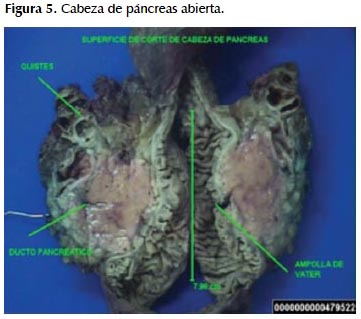

Se recibe fragmento de epiplon, segmento distal de estómago, duodeno, acompañado de cabeza de páncreas y colédoco. La cabeza de páncreas mide 8,6x4, 5x3,8 cm, páncreas de color pardo (Figura 5). Al corte se observa múltiples formaciones quísticas ubicadas en sus bordes superiores, en un área total de 5x2x2 cm conteniendo sangre y material mucoide, de paredes delgadas, algunos con proyecciones papilares.

Parénquima pancreático restante de color pardo-amarillento, ligeramente congestivo, conducto colédoco mide 6x0,6 cm permeable con estrechez a nivel de la ampolla de Vater, observándose además el conducto principal pancreático de 4 cm de longitud por 0,1 cm de diámetro mayor, permeable. Borde quirúrgico pancreático sin alteraciones macroscópicas; de la grasa peripancreática se disecan 20 ganglios linfáticos de 0,5 a 0,8 cm.